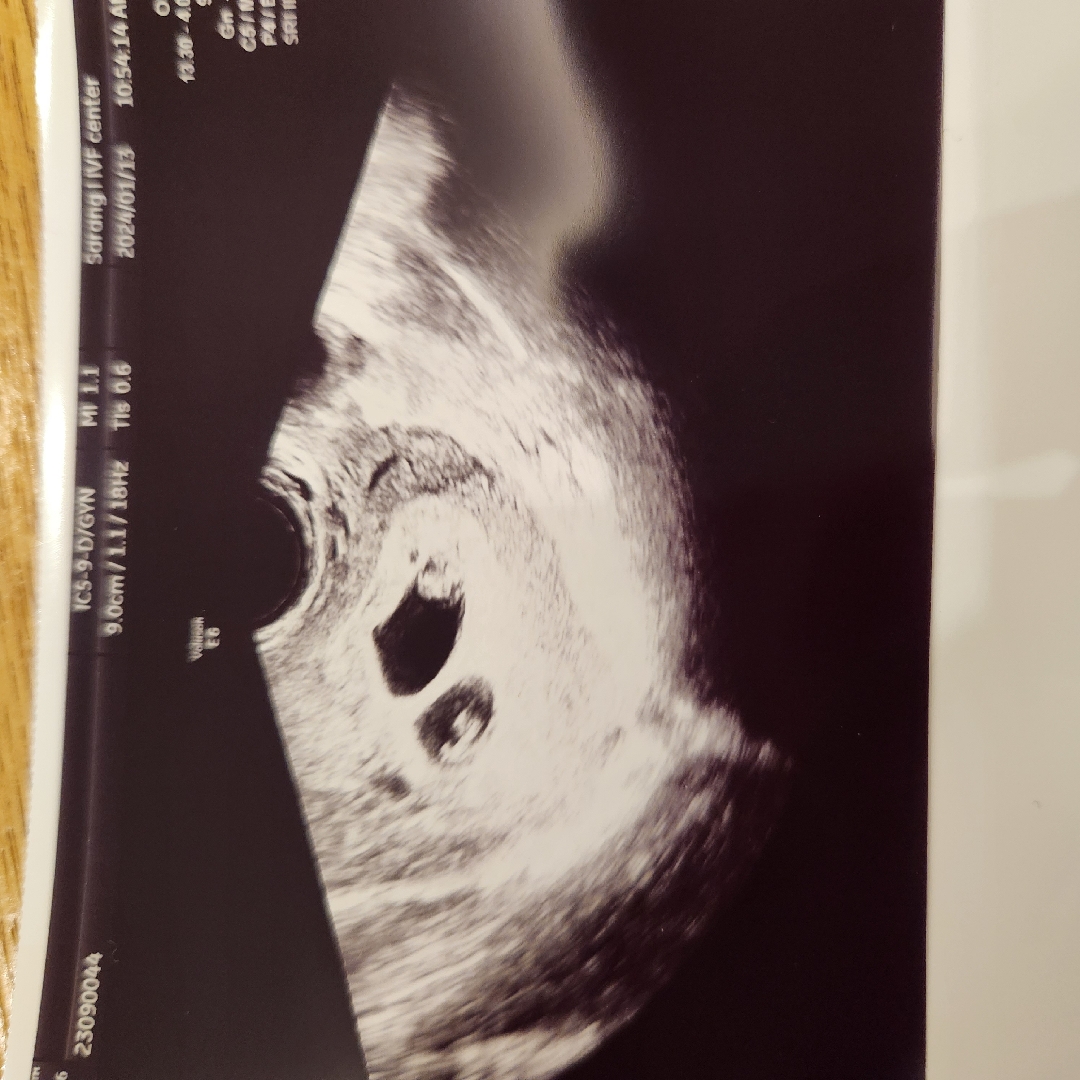

쌍둥이들 초음파 보고왔어요

심장소리듣는데 먼가 신기한 기분....... 근데 처음에 초음파 넣을 때 바로 애기집 세개보여서 너무 놀랬는데 애기집 하나는 그냥 따로 분열 된 것 같다 하셔서 ㅠㅜ 다행히 수술까진 안 갈 것 같아요.....ㅠㅜㅠㅠ